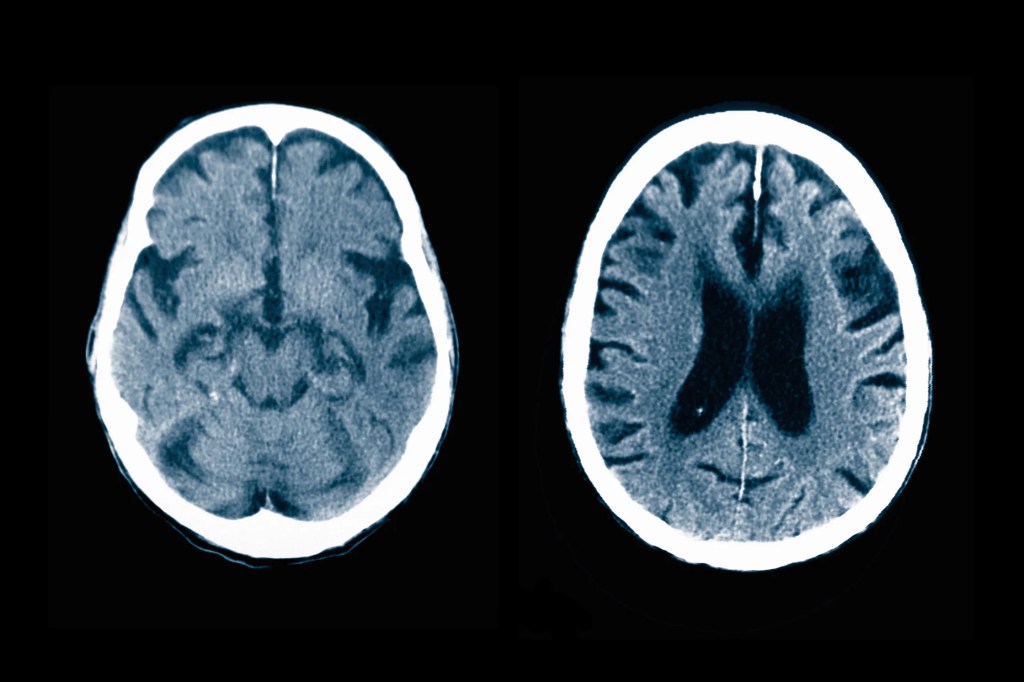

Millions of people over the age of 65 likely have mild cognitive impairment, or MCI—minor problems with memory or decisionmaking that can, over time, turn into dementia. But a pair of recent studies both concluded that 92 percent of people experiencing MCI in the United States are not getting diagnosed at an early stage, preventing them from accessing new Alzheimer’s treatments that may be able to slow cognitive decline if it’s caught soon enough.